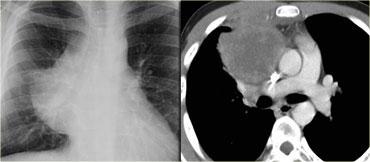

Hãy mô tả các hình ảnh bên trái.

Sau đó tiếp tục.

Trên phim thẳng (PA), có hình ảnh giãn rộng dạng múi của trung thất trên.

Trên phim nghiêng ngực, khoang sáng sau xương ức bị xóa mờ.

Đây là trường hợp bệnh nhân mắc u lympho.